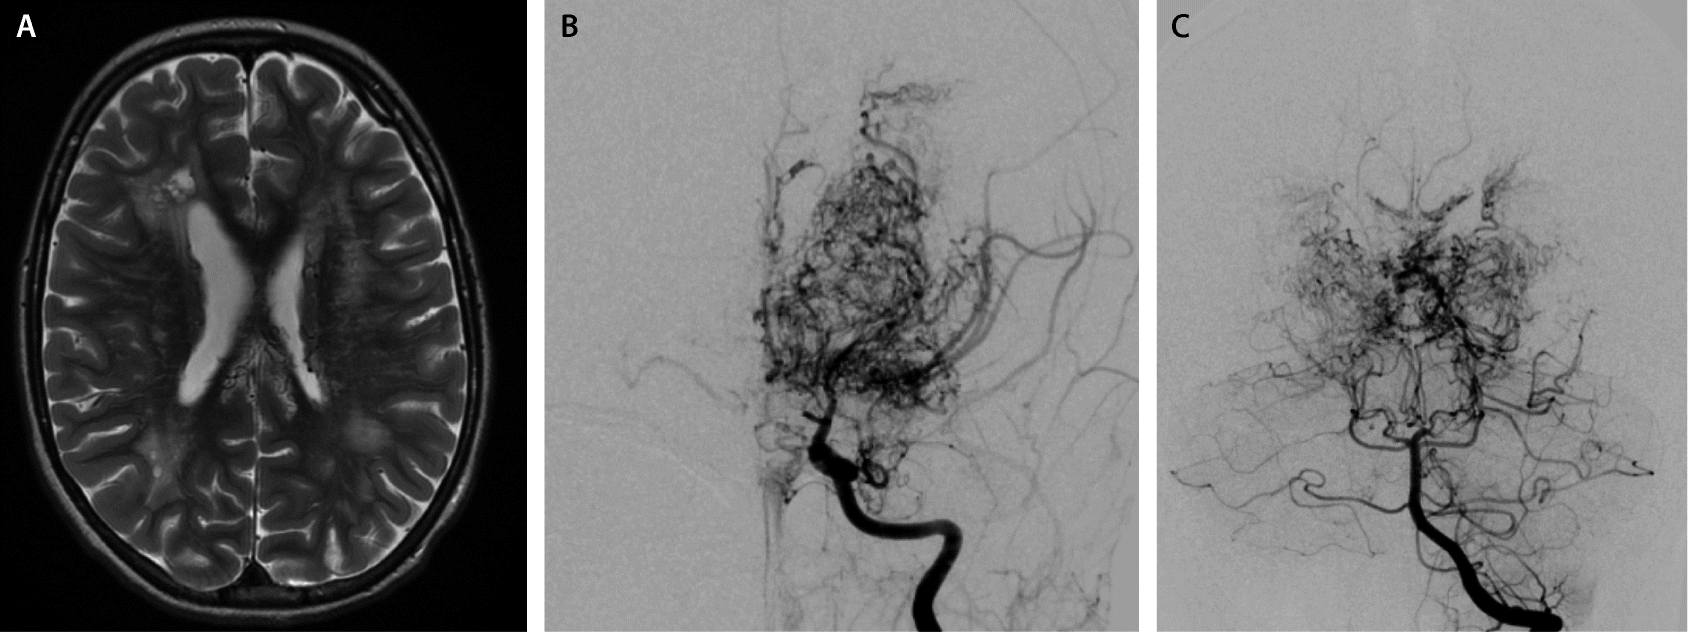

Abb 4 8 Moyamoya Erkrankung Download Scientific Diagram

Diagnostik Und Therapie Der Moyamoya Erkrankung